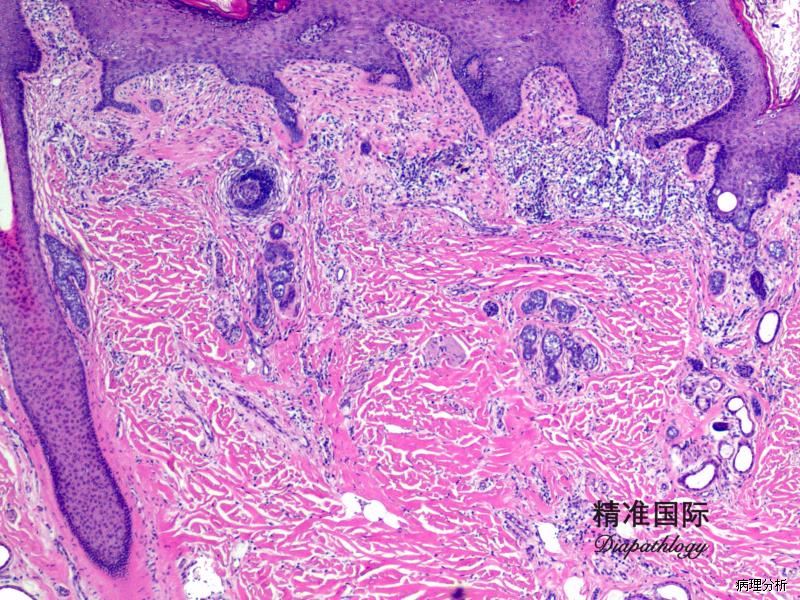

皮脂腺痣

发病部位: 头皮或面部

诊断要点:

1. 通常出生即有或儿童早期即可出现,表现为头皮或面部孤立性橘黄色斑块;

2. 镜下见分化成熟的皮脂腺数量增加,腺体可直接插入到表皮内;

3. 毛囊本身可数量减少或形状异常;

4. 可伴有大汗腺数量增加;

5. 表皮可呈表皮痣样改变;